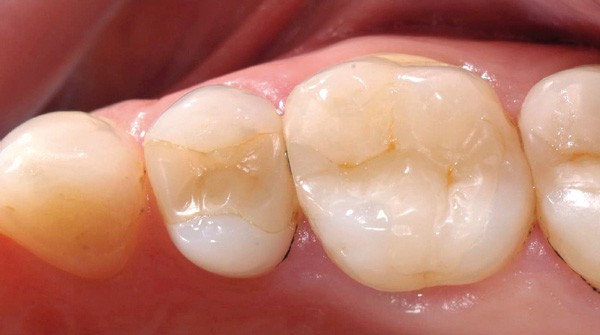

L’omnipraticien est très souvent confronté à cette question lors de sa pratique quotidienne : quel est le bon moment pour adresser les enfants chez l’orthodontiste ? La réponse peut recéler quelques difficultés, car elle est spécifique à chaque enfant. Le temps où il était conseillé d’attendre la denture définitive pour intervenir est révolu : certaines interventions précoces permettent aujourd’hui dans certains cas de raccourcir et de simplifier les traitements orthodontiques. C’est notamment le cas des anomalies transversales, qui sont celles qui sont traitées le plus précocement, dès 6 ans. Ainsi, lors d’anomalie cliniquement évidente, la consultation orthodontique s’impose. Cependant, certaines anomalies sont plus discrètes, et donc plus difficiles à dépister. Une panoramique doit toujours être réalisée en première intention afin de dépister les agénésies. Puis, même en l’absence d’anomalie évidente, il est recommandé d’adresser les enfants chez l’orthodontiste entre 7 et 9 ans : celui-ci sera ainsi à même d’adapter la prise en charge, et surtout l’âge idéal de prise en charge pour chaque patient(fig. 3 et 4).